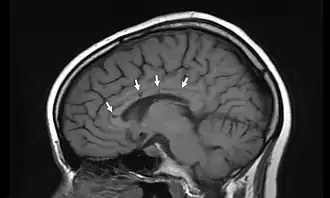

К основным признакам синдрома Сусака относят двустороннюю нейросенсорную тугоухость, ишемическую ретинопатию и подострую энцефалопатию, однако на ранних стадиях могут присутствовать не все признаки данной триады, что значительно осложняет диагностику. При проведении инструментальной диагностики на себя обращают внимание множественные очаги, в отличие от системных васкулитов накапливающие контраст, в перивентрикулярной зоне, мозжечке и мозолистом теле, редко — единичные очаги в сером веществе головного мозга. Отсутствие очагов в спинном мозге позволяет проводить дифдиагностику с рассеянным склерозом. Изменения сосудов сетчатки с признаками окклюзии артериол и без признаков демиелинизирующих процессов тоже характерны для заболевания[3]. В 2017 году американские ученые Университета Мэриленд установили, что синдром Сусака был той загадочной болезнью[4], которой страдал испанский художник Франсиско Гойя, и которая послужила причиной глухоты, поразившей художника в 1793 году [5].